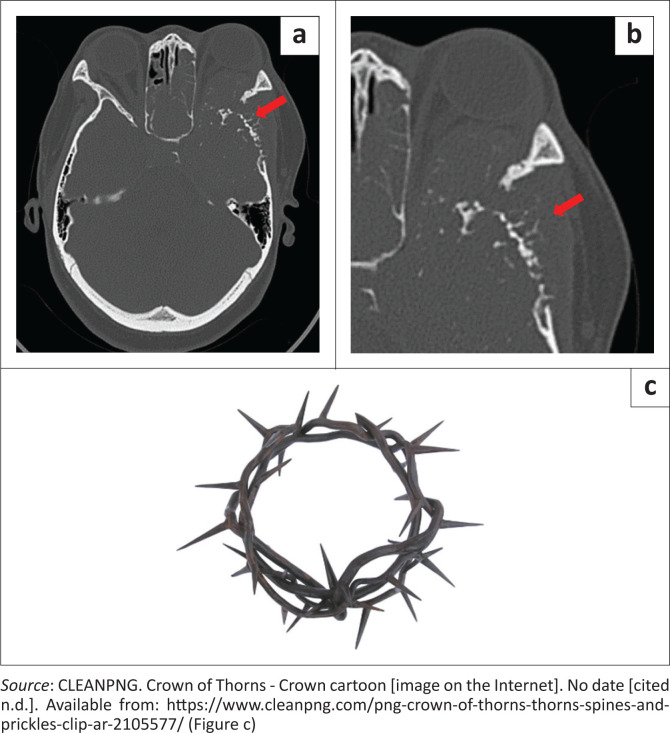

Plasma cell neoplasia has a wide presentation of disease (localised or systemic) according to the International Myeloma Working Group. Radiological imaging identifies plasmacytomas as solitary lesions or part of multiple myeloma. We present a rare case of a 21-year-old female who presented with a skull-base tumour.

Contribution: A head and neck plasmacytoma with further lytic bone lesions was confirmed on imaging. This article presents and discusses the clinical, CT, MRI, positron emission tomography (PET)-CT, histology and laboratory findings.